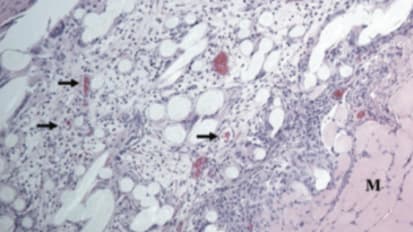

Learn more about the GORE® BIO-A® Web Technology, and how it works as a scaffolding to help the body grow vascularized soft tissue.Biosynthetics — Know your options